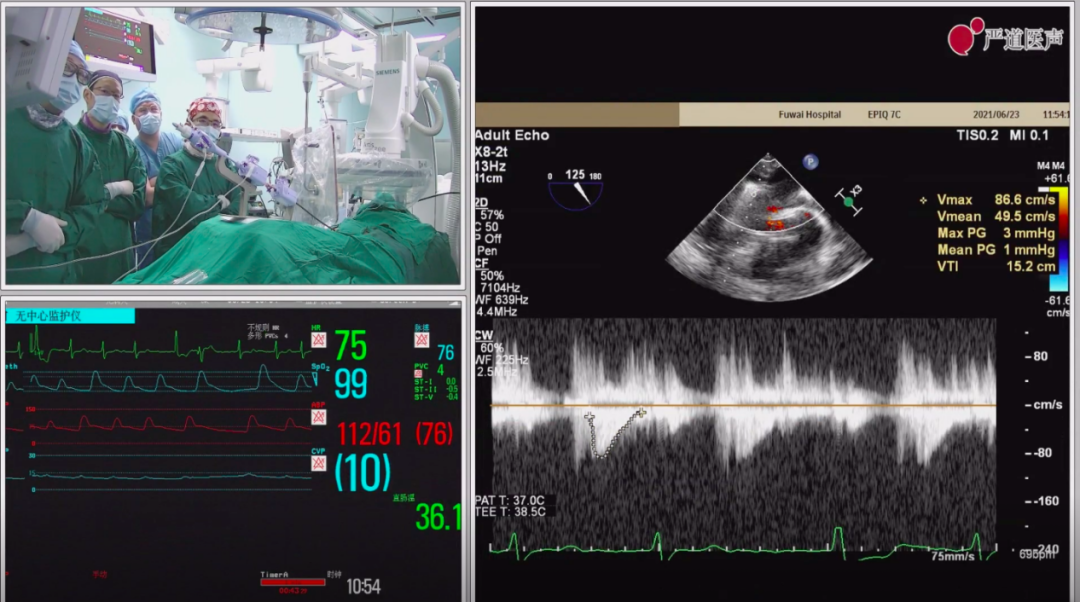

二尖瓣夹释放后,超声显示反流几近消失,患者各项生理指标正常,手术顺利完成,手术操作耗时约60 min。

患者术后超声检测及生命体征